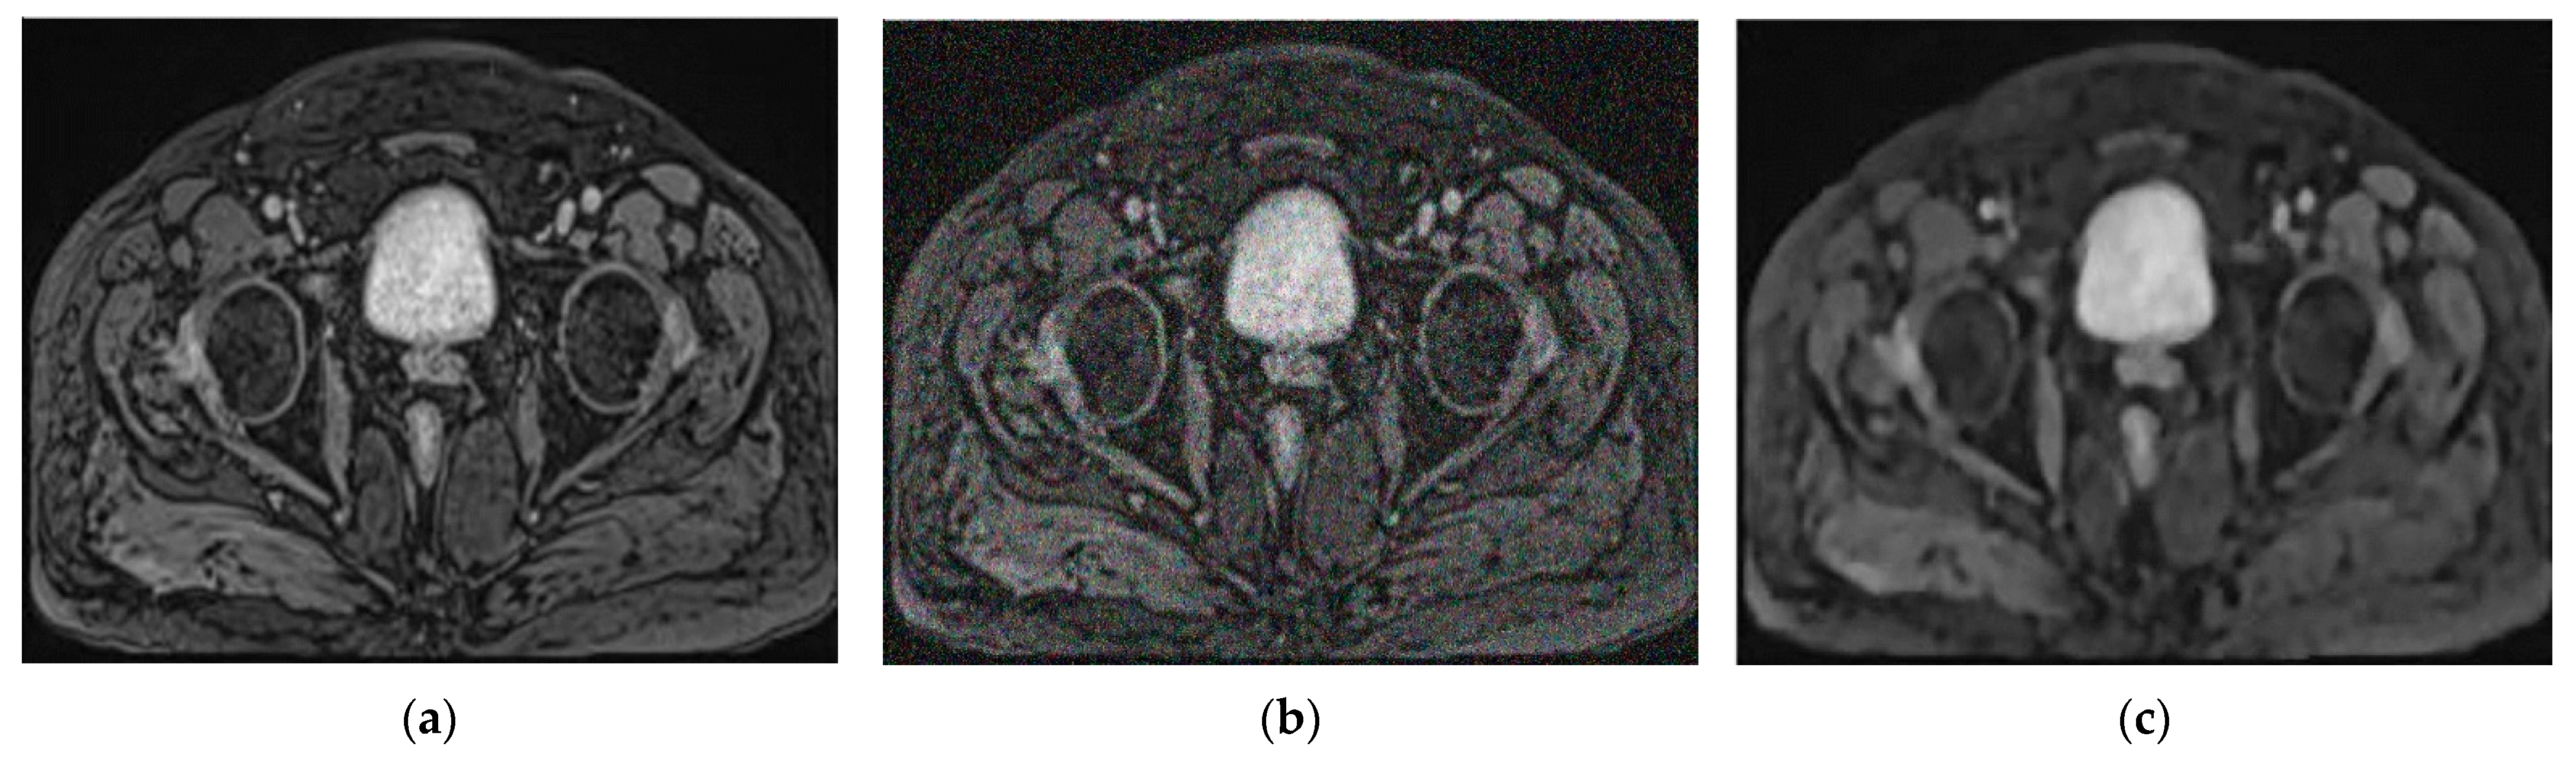

2.2.1. Gaussian Noise Insertion into Images

2.2.2. Multi-Scale Denoising Convolutional Neural Network (MSDCNN)